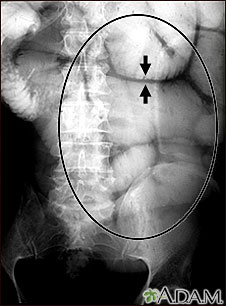

Exams and Tests

During a physical exam, the health care provider may find bloating, tenderness, or hernias in the abdomen.

Tests that show obstruction include:

- Abdominal CT scan

- Abdominal x-ray

- Barium enema

- Upper GI and small bowel series